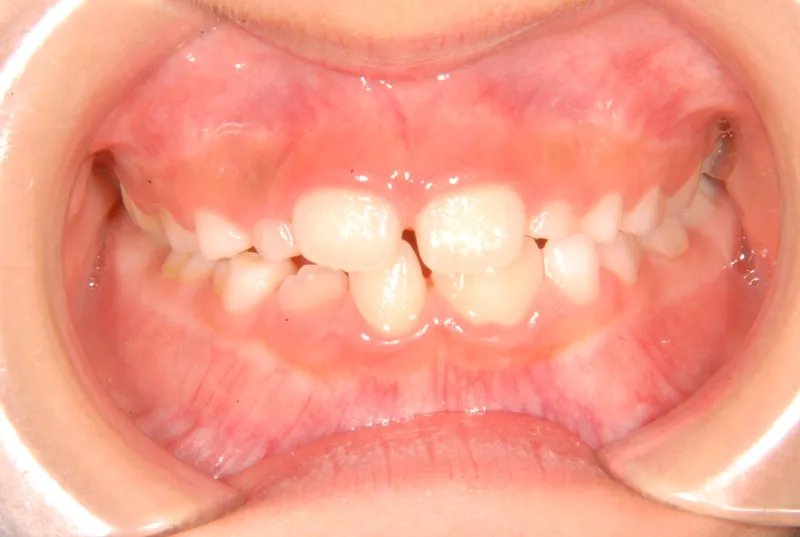

初診時年齢 小学校2年生 (男性) 主訴 癒合歯・永久歯が生えるスペースがない

診断名 叢生 装置名

上下の歯並びが狭く、永久歯の生える隙間がありません。

右下に癒合歯があり 上下の歯並びのアーチが悪くなっています。

状態 永久歯が生える隙間がない(叢生)

ガタガタ・でこぼこに生えている(叢生)